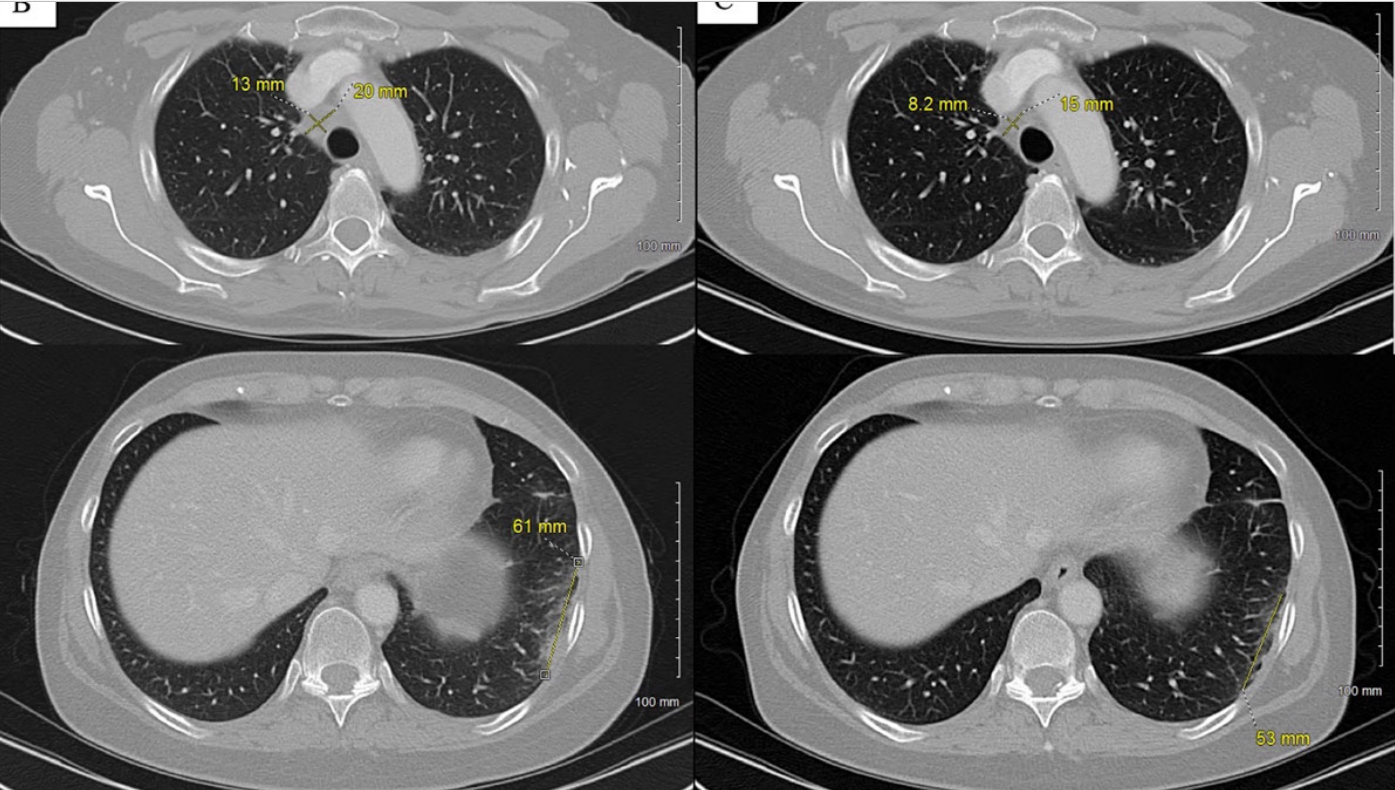

近日,《Frontiers in Oncology》发表了拉罗替尼治疗NTRK融合肿瘤儿童的病例报告。

一名曾因NTRK基因融合阳性肿瘤而命悬一线的5岁女童,在接受了靶向药物佐来曲替尼的治疗后重获新生。她从一度住进ICU、呼吸困难的危急状态,迅速好转,一周内症状缓解,如今“能跑能跳,和正常小朋友没两样”。在用药15个月的时间里,该患儿疗效一直很稳定。